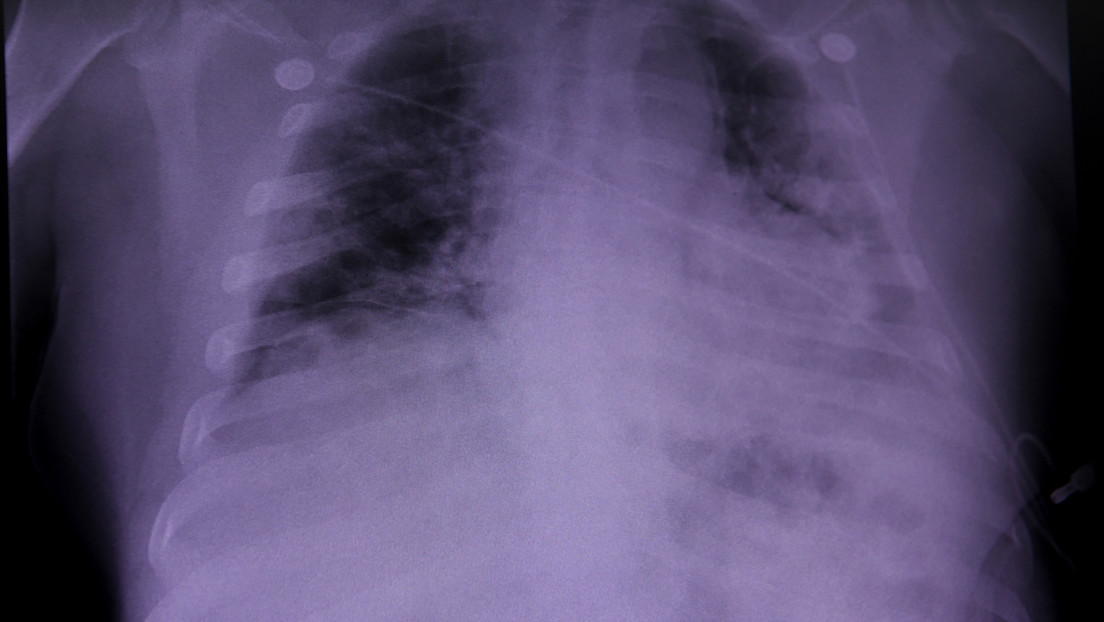

Durante el estudio, que fue publicado este martes en EBioMedicine, los científicos analizaron muestras de tejido pulmonar, hepático y renal de 41 pacientes que fallecieron a causa del coronavirus en el Hospital Universitario de Trieste (Italia) al inicio de la pandemia, entre febrero y abril de 2020.

Tras los análisis, los investigadores identificaron que el 90 % de las personas estudiadas mostraron una extensa coagulación de la sangre de las arterias y venas del pulmón (trombosis), así como la presencia de varias células pulmonares anormalmente grandes y con muchos núcleos, producto de la fusión de diferentes células en una sola célula grande, ambos síntomas característicos del covid-19 en comparación con otras formas de neumonía.

Por su parte, Mauro Giacca, coautor del estudio, apuntó que no se encontraron signos de infección viral o inflamación prolongada en otros órganos, y que identificaron "una destrucción realmente vasta de la arquitectura de los pulmones", en la que el tejido pulmonar sano fue "casi completamente sustituido por el tejido cicatricial".